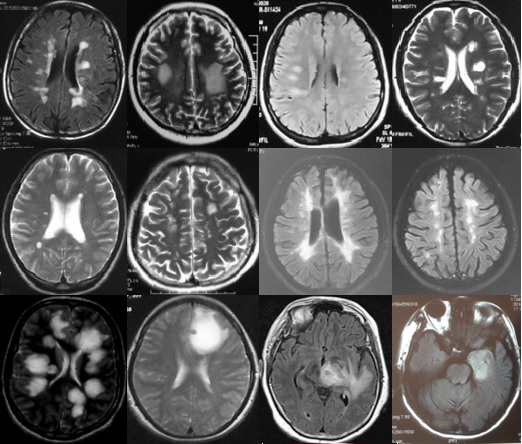

重要申明:以下每个部分会配磁共振图片,因疾病和影像之间存在同病异象、同像异病,为避免误导,图片不标注疾病,请各自鉴赏,另其中有部分图片来源于网络,有疑问可与本人联系。

I--inflammation,炎症

脱髓鞘,多发性硬化(MS)、视神经脊髓炎(NMO)、急性播散性脑脊髓炎(ADEM)、MOG相关性脱髓鞘病变、自身免疫性脑炎、CNS血管炎、神经系统结节病、Susac's Syndrome、Clippers’综合症、桥本氏脑病等。还有如急性、亚急性的放疗损伤等。

N--neoplasm,肿瘤

各种肿瘤,如胶质瘤、淋巴瘤、脑膜瘤、血管内淋巴瘤,生殖细胞瘤、各种转移瘤、心房粘液瘤等。神经纤维瘤病也可在中枢出现影像学上类似脱髓鞘的病变。

I--infection,感染

指的是各种感染,病毒(单纯疱疹病毒、带状疱疹…)、细菌(革兰阳性、革兰阴性、球菌、杆菌…)、结核、。真菌、梅毒、各种寄生虫(囊虫、弓形虫、吸虫、裂头蚴等)。还有进行性多灶性白质脑病(PML)、CJD、Whipple’s 病等。亚急性细菌性心内膜炎。